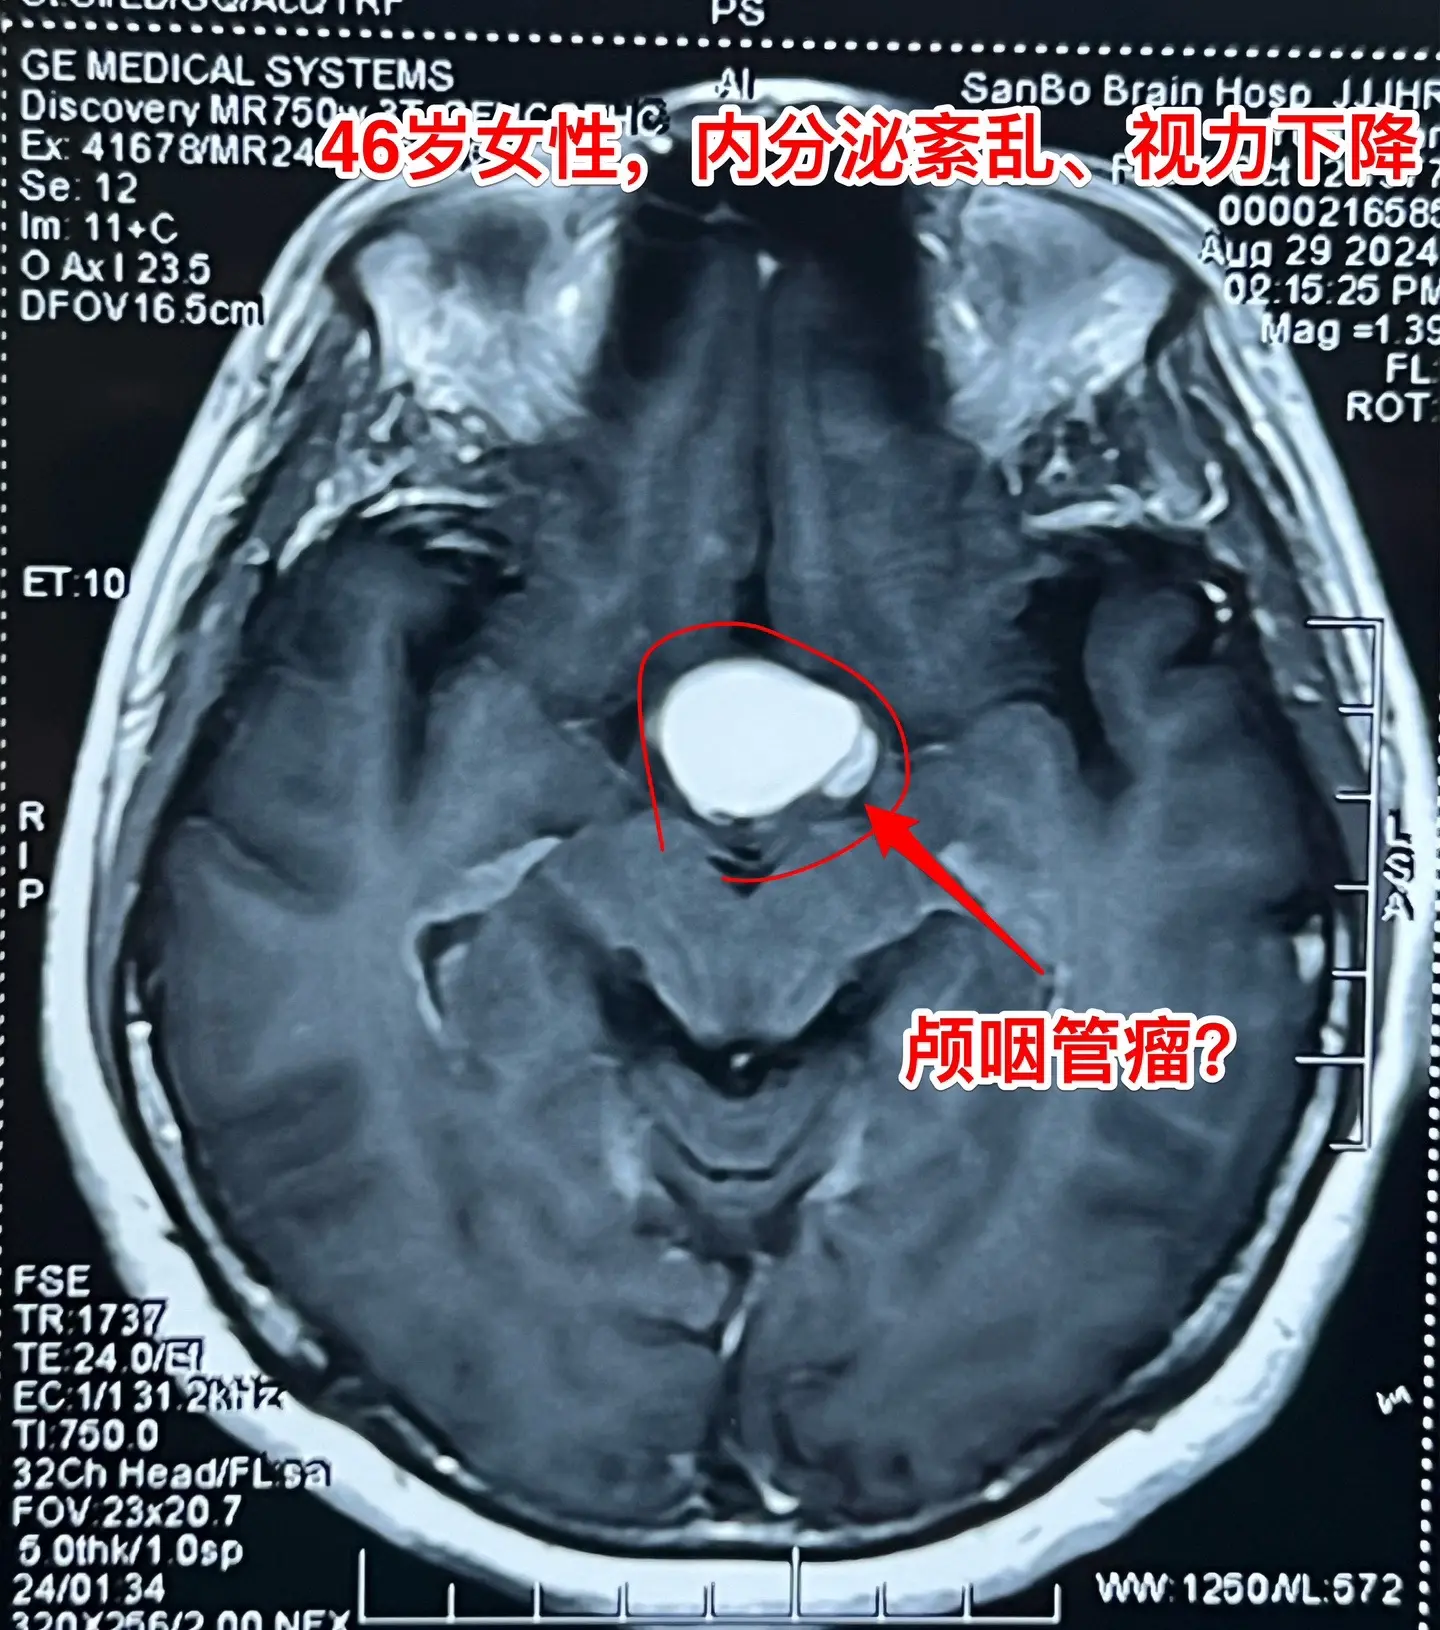

颅咽管瘤与拉克氏囊肿好鉴别吗?典型的造釉细胞型颅咽管瘤有钙化,与拉克氏囊肿容易鉴别。 典型的乳头型颅咽管瘤有明显的强化灶,与颅咽管瘤也好鉴别。 不典型的颅咽管瘤与拉克氏囊肿就很难鉴别了。 这个46岁的女性因为内分泌紊乱、视力下降、精神差等症状到医院检查发现鞍区病变,怀疑是颅咽管瘤,遂到我科住院治疗。 CT见鞍区囊性病变,没有看见明显的钙化。磁共振显示鞍区囊性病变,强化扫描未见明显强化。 我们怀疑是拉克氏囊肿。9月3日作手术过程中,未见病变内钙化,亦未见乳头型肿瘤结节。 手术后三天病理报告显示是造釉细胞性颅咽管瘤。